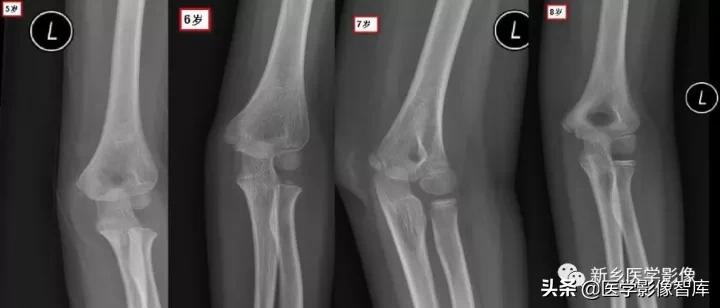

肘关节骨骺

现在简单了,只要记住CRI TOE1-3-5-7-9-11就行了:

- Capitellum (appears age 1-2)肱骨小头1 year - Radial Head (appears age 2-4)桡骨小头 3years- Interanal epicondyle (appears age 4-6)内上髁 5years- Trochlea (appears age 8-11)滑车 7years- Olecranon (9-11 years)鹰嘴 9years- External epicondyle (appears age 10-11)外上髁 11years